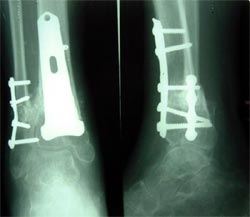

图1-2 将异体骨裁剪成12厘米长的骨板,将患者自体骨髓细胞经特殊处理后,

与松质骨和骨生长因子复合,形成成骨细胞和提供支撑力巧妙集合在一起的复合物,

使没有细胞的植骨材料变成了有细胞的活骨,新骨形成的效果得以大大加强。

图1-3 将异体骨--患者自体骨髓细胞---松质骨和骨生长因子复合物植入